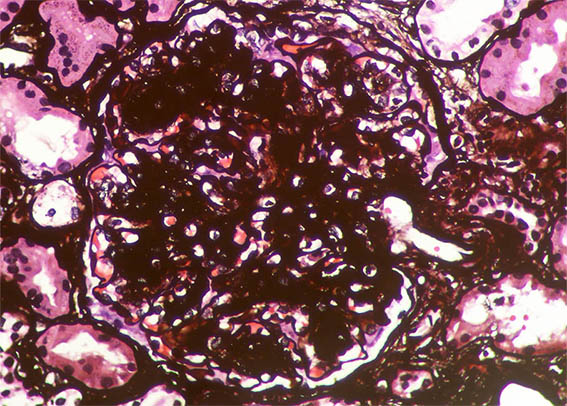

Figura 8. Plata-metenamina, X400.

Figura 9. Plata-metenamina, X400.

Figura 10. Plata-metenamina, X400. Observe el nódulo de la parte superior derecha, rodeado por membrana basal (posiblemente microaneurisma con trombo en organización).